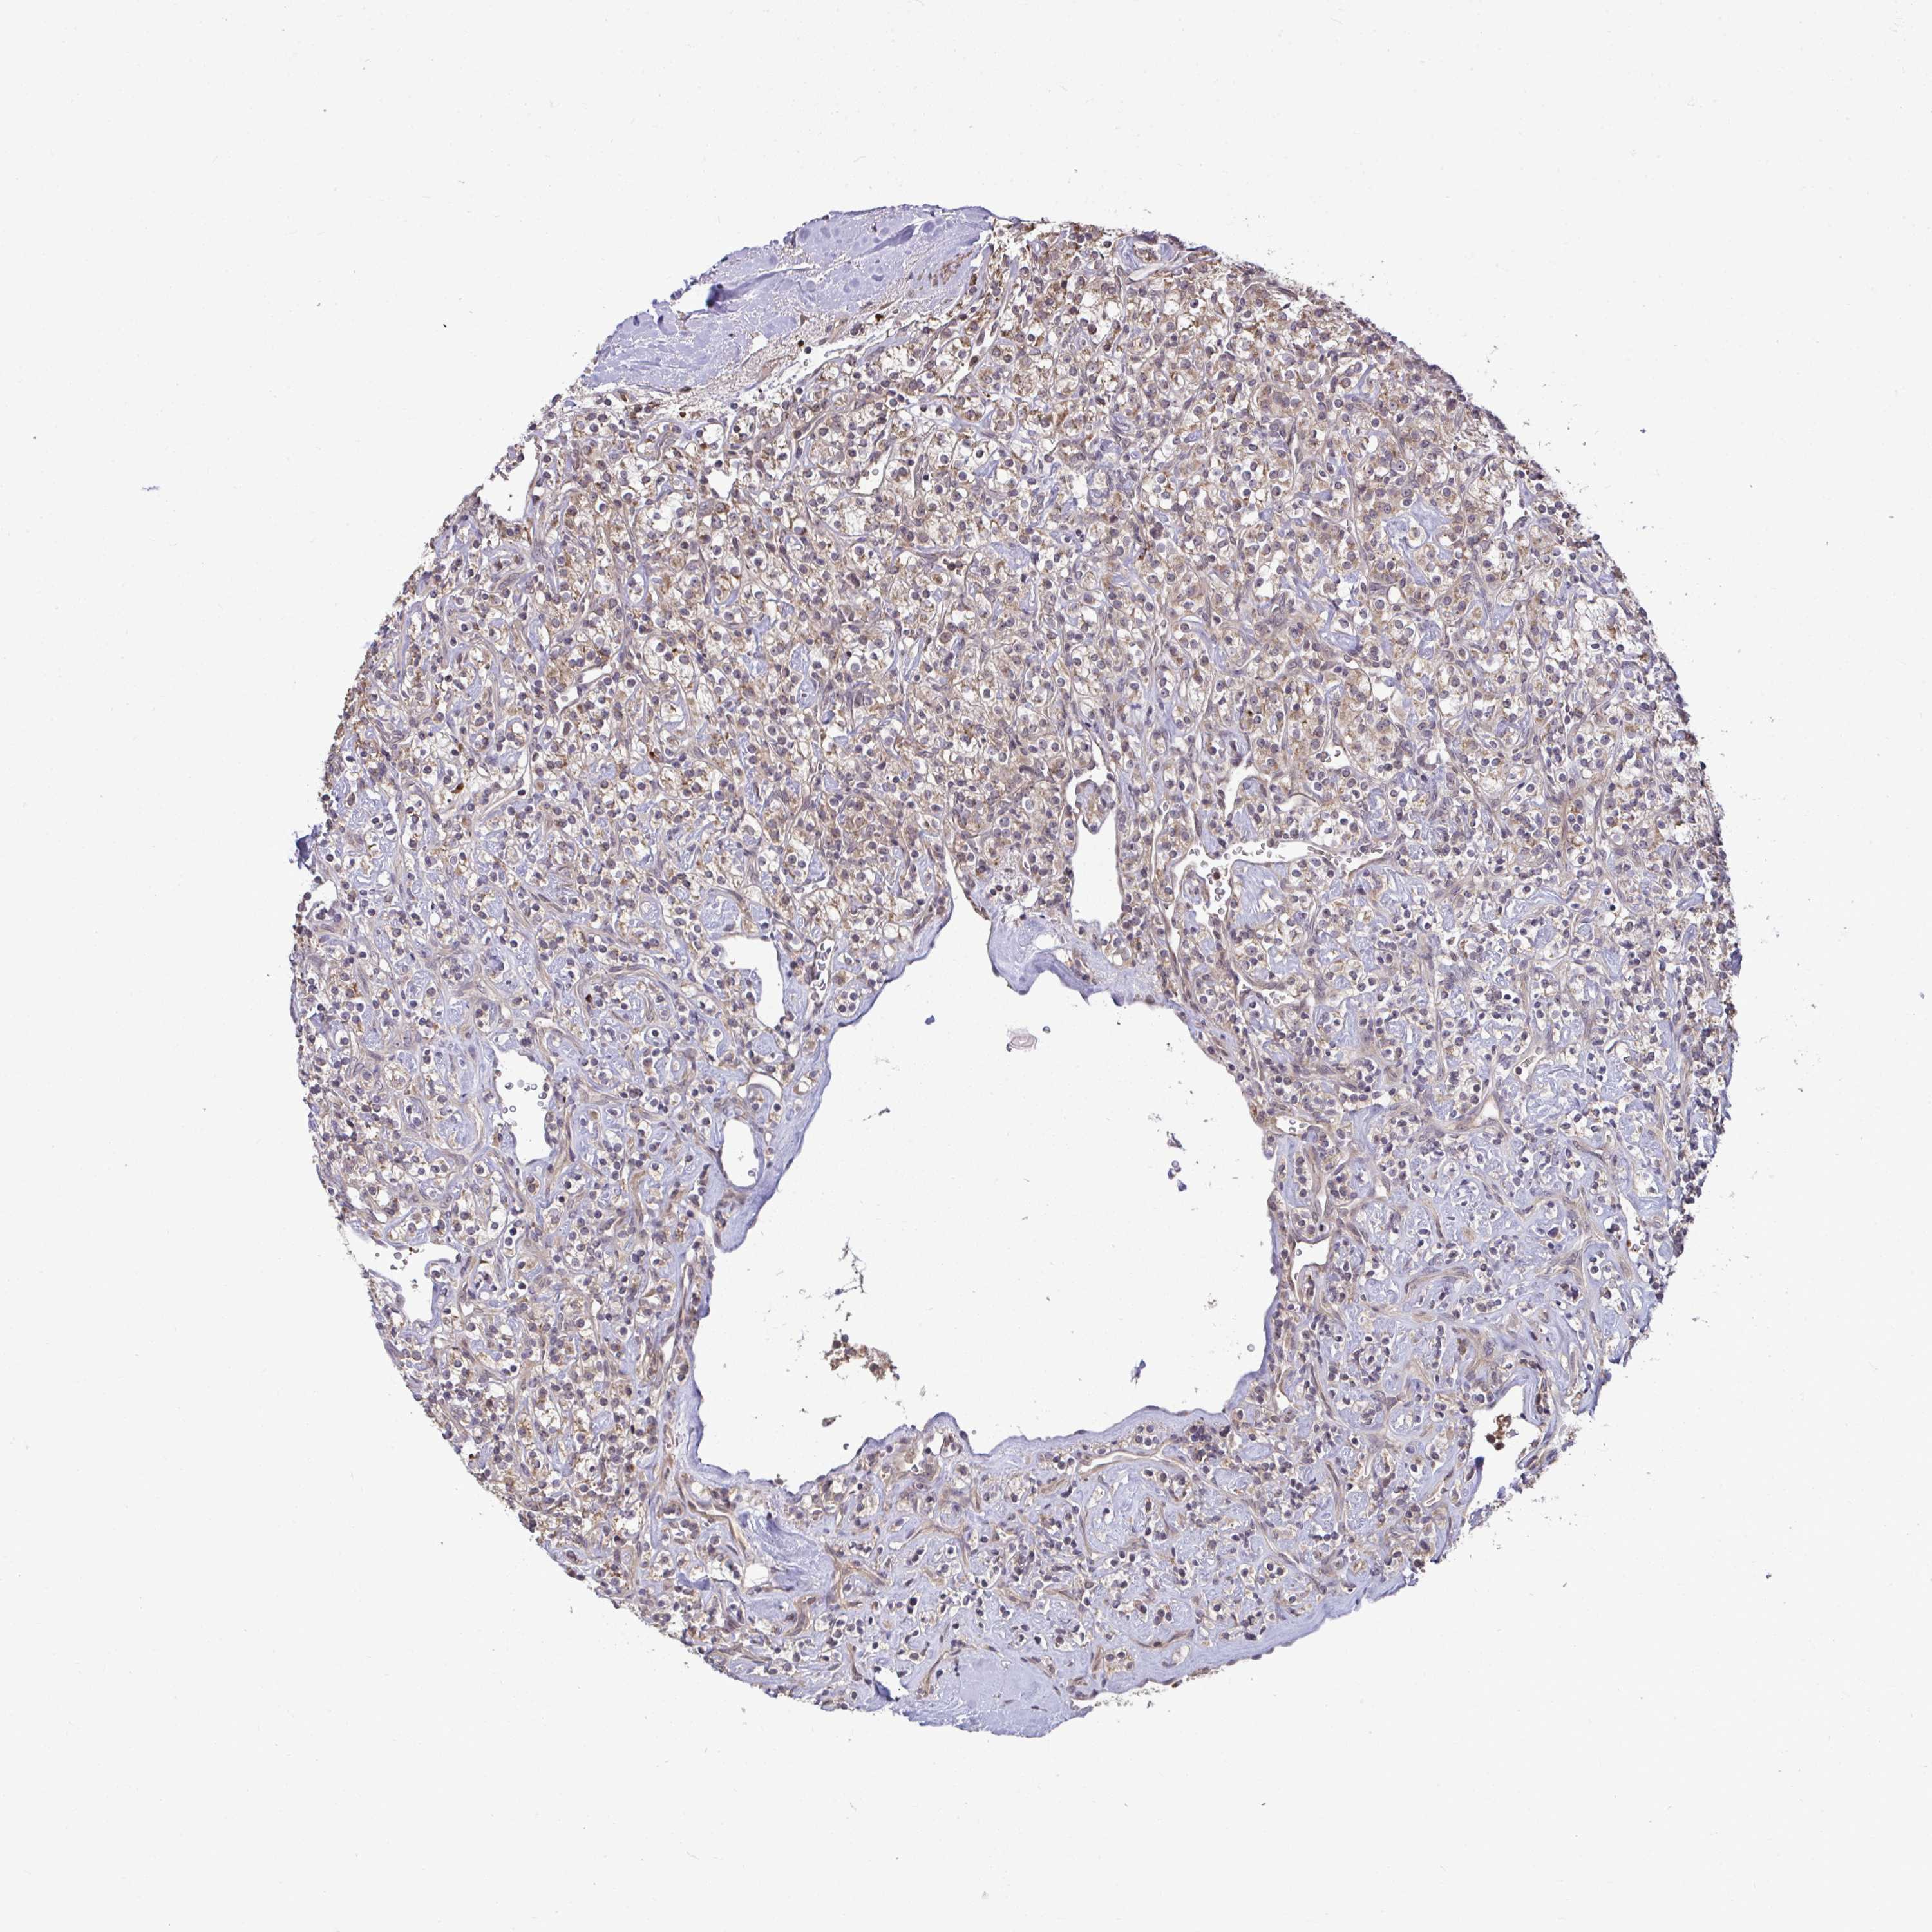

KIDNEY RENAL PAPILLARY CELL CARCINOMA (TCGA) - Interactive survival scatter ploti

The Survival Scatter plot shows the clinical status (i.e. dead or alive) for all individuals in the patient cohort, based on the same data that underlies the corresponding Kaplan-Meier plots. Patients that are alive at last time for follow-up are shown in blue and patients who have died during the study are shown in red.

The x-axis shows the expression levels (FPKM) of the investigated gene in the tumor tissue at the time of diagnosis. The y-axis shows the follow-up time after diagnosis (years). Both axes are complimented with kernel density curves demonstrating the data density over the axes. The top density plot shows the expression levels (FPKM) distribution among dead (red) and alive patients (blue). The right density plot shows the data density of the survived years of dead patients with high and low expression levels respectively, stratified using the cutoff indicated by the vertical dashed line through the Survival Scatter plot. This cutoff is automatically defined based on the FPKM cutoff that minimizes the p-score. The cutoff can be changed by dragging the vertical line or by entering a cutoff value in the square labeled "Current cut-off".

Under the Survival Scatter plot the p-score landscape (black curve; left axis) is shown together with dead median separation (red curve; right axis). Dead median separation is the difference in median mRNA expression between patients who have died with high and low expression, respectively. It is calculated as follows: median FPKM expression of dead patients with high expression - median FPKM expression of dead patients with low expression. This is intended to aid the user in visually exploring custom cutoffs and the associated p-scores and dead median separation.

Individual patient data is displayed and can be filtered by clicking on one or more of the category buttons on the top of the page. Categories describing expression level and patient information include: high, low, alive, dead, female, male and tumor stages. The scale of the x-axis can be toggled between linear and log-scale by clicking on the "x log" button. Mouse-over function shows TCGA ID, patient information and mRNA expression (FPKM) for each patient.

& Survival analysisi

Kaplan-Meier plots summarize results from analysis of correlation between mRNA expression level and patient survival. Patients were divided based on level of expression into one of the two groups "low" (under cut off) or "high" (over cut off). X-axis shows time for survival (years) and y-axis shows the probability of survival, where 1.0 corresponds to 100 percent.

ZSCAN9 is not prognostic in Kidney Renal Papillary Cell Carcinoma (TCGA)

Best expression cut offi

Based on the FPKM value of each gene, patients were classified into two groups and association between prognosis (survival) and gene expression (FPKM) was examined. The best expression cut-off refers the FPKM value that yields maximal difference with regard to survival between the two groups at the lowest log-rank P-value. Best expression cut-off was selected based on survival analysis .